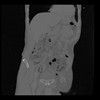

35 CUERPO,CE,Coronal,3.000,CUERPO,Coronal,